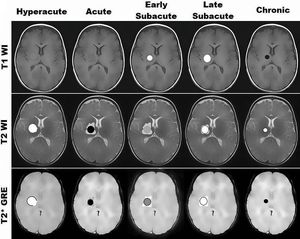

Stages of brain hemorrhage in MRI.

Mri

Hemorrhage

T2w

T1w

T2 Star